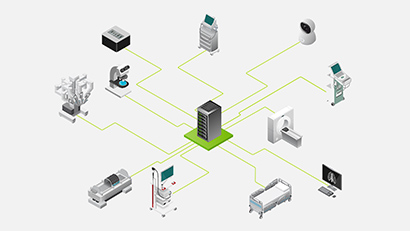

Smart Hospitals und medizinische Instrumente

Von intelligenten Sensoren bis hin zu medizinischen Instrumenten, die fortschrittliche Bildverarbeitung in Echtzeit unterstützen, kann KI am Rand unmittelbare Erkenntnisse liefern, die Patientenversorgung optimieren und das Versprechen von intelligenten Krankenhäusern verwirklichen.

Die Edge Solutions von NVIDIA sind darauf ausgelegt, kontinuierliche Datenströme am Netzwerkanrand zu erfassen und zu berechnen. Mit fortschrittlicher Bild-, Video-und Signalverarbeitung können in der Ki eingebettete medizinische Instrumente Chirurgen bei der Ausführung von weniger invasiven, gezielteren Operationen, Radiologen bei der Ermittlung von Diagnosen und Sonographen bei der Ausführung schneller und präziser Echokardiogramme schützen. Mit der NVIDIA EGX Platform können Sie das Gesundheitswesen auf den neuesten Stand bringen.

Erstellen Sie domänenspezifische medizinische Anwendungsgebiete

NVIDIA Clara™ ist ein Framework für medizinische Anwendungen für bildgebende Bildgebung, Genomik sowie die Entwicklung und Bereitstellung von Intelligente Sensoren und mit Ki aktivierte medizinische Geräte. Sie umfasst eine ganze Reihe grafikprozessorbeschleunigter Bibliotheken, SDKs und Referenzanträge für Entwickler, Datenwissenschaftler und Forscher, um Echtzeitanwendungen für sichere und skalierbare Lösungen zu erstellen.